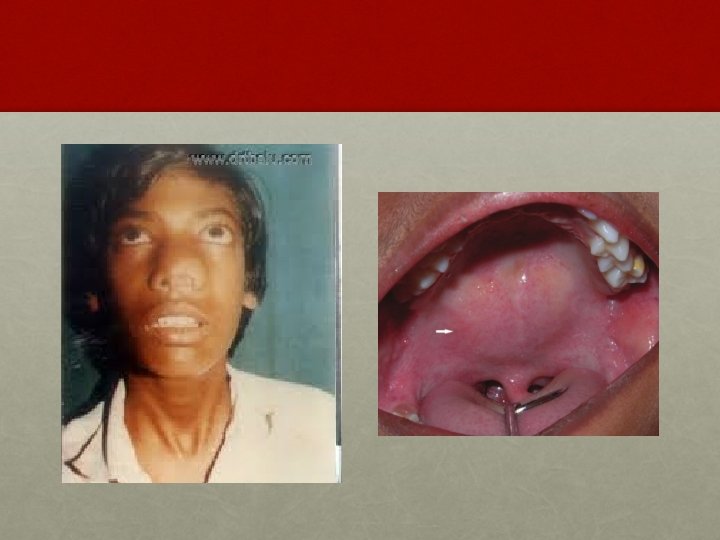

CLINICAL FEATURES: § Profuse and recurrent epistaxis. § Progressive nasal obstruction and hyponasal voice. § Conductive hear loss and middle ear effusion. § Extension of tumor in different directions produces symptoms like facial swelling, proptosis, diplopia, broadening of nasal bridge, palatal buldge and cranial nerve palsies.